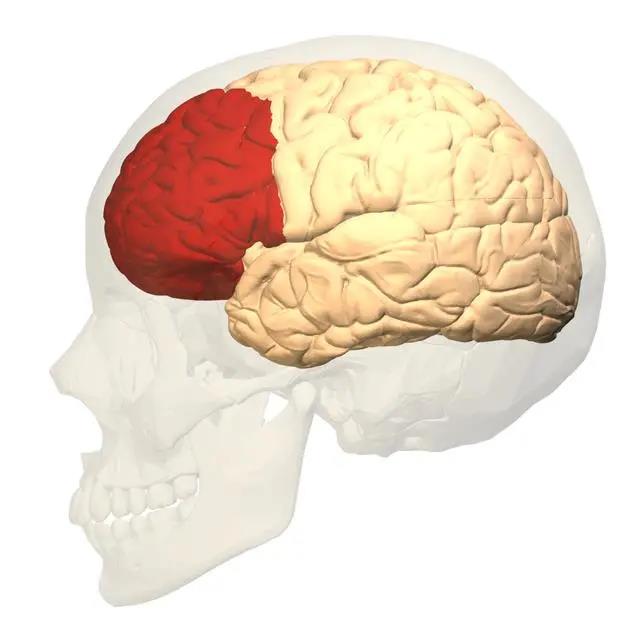

在我們的大腦結(jié)構(gòu)中,有一塊區(qū)域叫做前額葉皮層,它負(fù)責(zé)調(diào)節(jié)人的思維和行為。對(duì)于年幼的孩子來(lái)說(shuō),前額葉皮層還處在發(fā)育階段,功能性較弱。

家長(zhǎng)在吼孩子的時(shí)候,孩子是會(huì)感到焦慮和恐懼的,當(dāng)前額葉皮層收到這種“危險(xiǎn)信號(hào)”時(shí),就會(huì)出現(xiàn)目光呆滯、逃避等行為。如果孩子長(zhǎng)期處在這種環(huán)境中,那么思維和行為都會(huì)出現(xiàn)問(wèn)題。

紅色區(qū)域?yàn)榍邦~葉